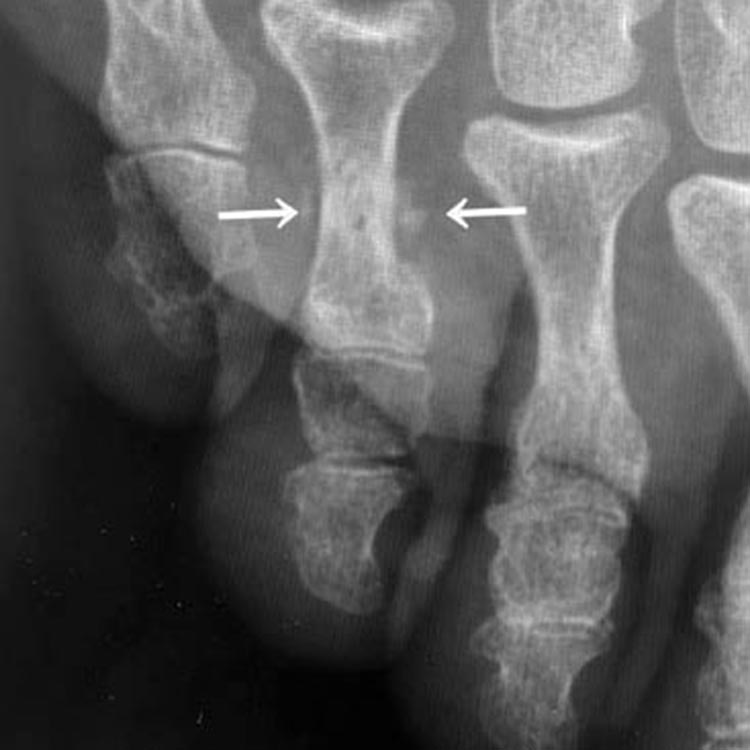

受傷1週後のレントゲン写真

受傷1週後(矢印が骨折部です)